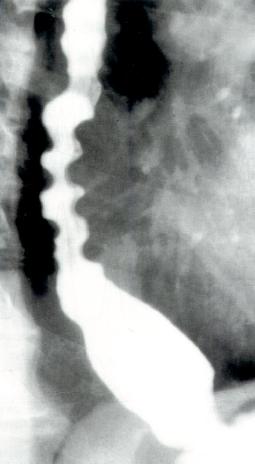

食管X线检查

X线吞钡可用于观察食管并显示食管是否扩张。贲门失弛缓症的特征性X线表现为胸部食管扩张伴液平。LES逐渐变细使食管呈现鸟嘴样外观(图2.7)。

贲门失弛缓症的食管X线表现

图2.7贲门失弛缓症的食管X线表现。